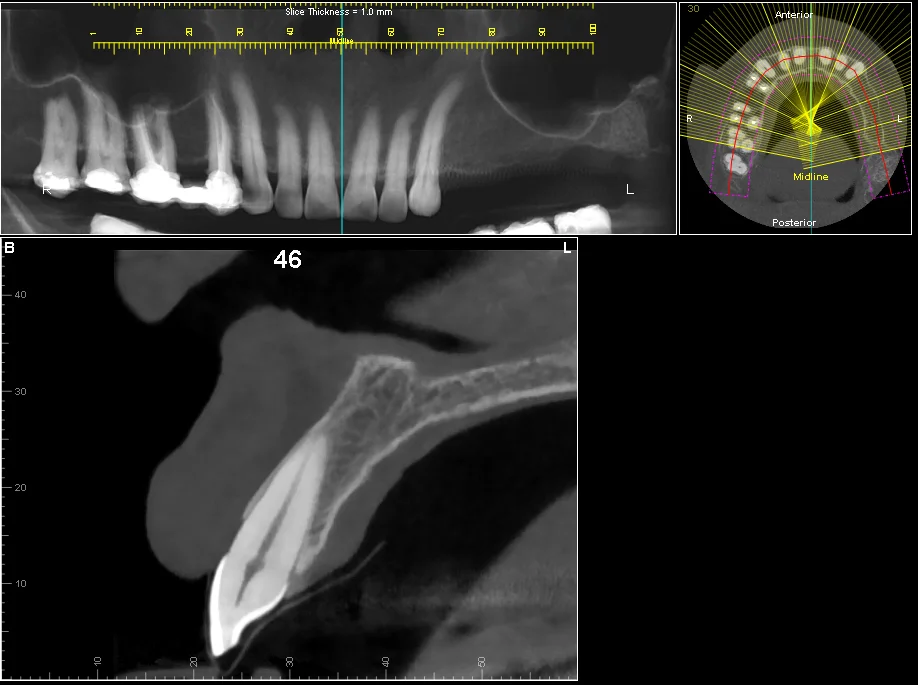

Cross-sections

Accurate cross-sections for accurately measuring bone height and width.